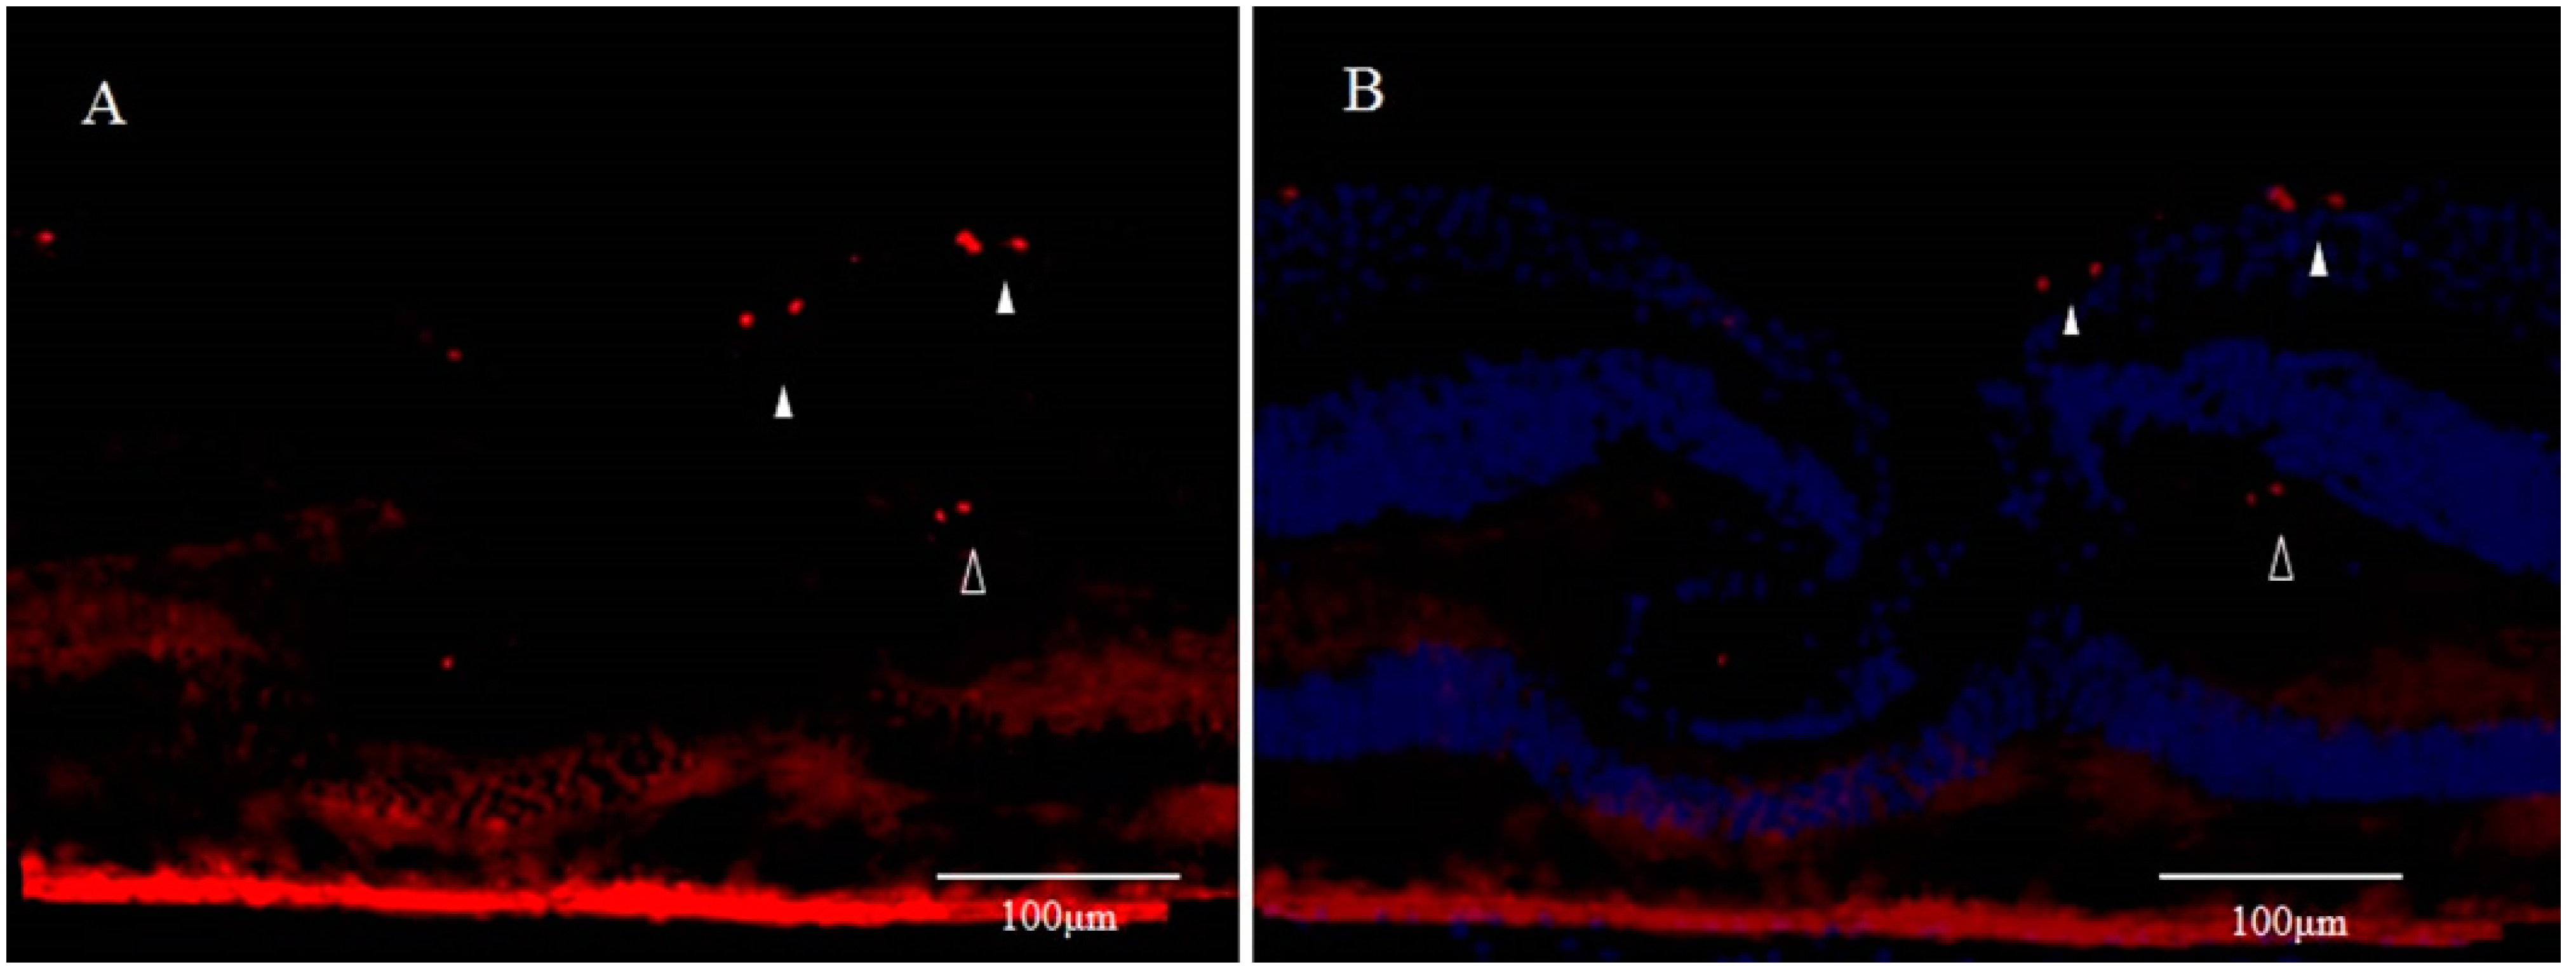

3. Involvement of Anoikis in the Pathogenesis of DONFL Appearance

3.1. Anoikis and Eye Diseases

3.2. Anoikis and Glial Cells

3.3. β. A3/A1-Crystallin and Anoikis

3.5. Anoikis and Retinal Ganglion Cells